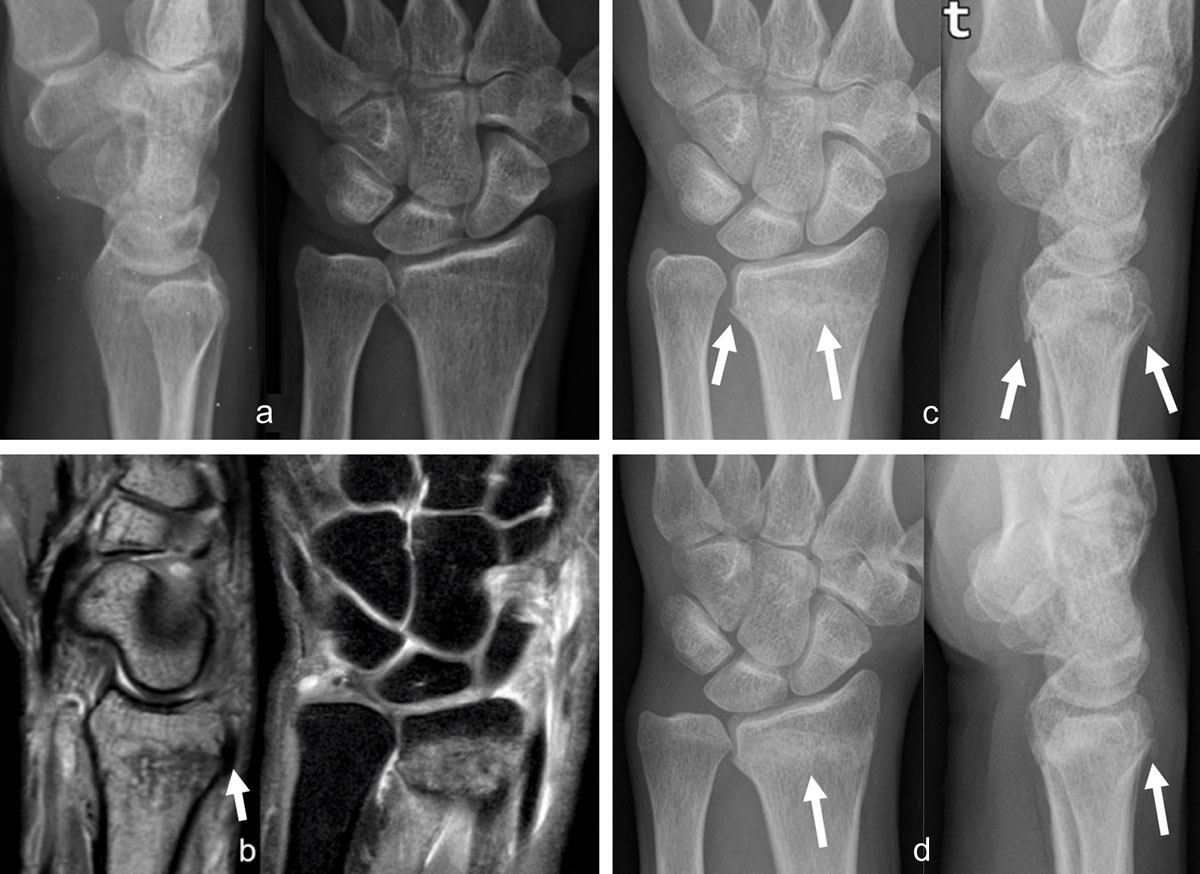

Figure 1

Occult radius fracture detected by MRI. The radiographs, (a) lateral and anteroposterior views, obtained the day after trauma were negative. Three days later, sagittal PD and coronal PDFS, (b) MR images revealed a nondisplaced radius fracture with extensive bone marrow edema and posterior cortical irregularity on the sagittal view (arrow). Control radiographs (AP and lateral views) obtained one month (c, arrows) and two months (d, arrows) post trauma depict consolidation signs, better seen on d (arrow).